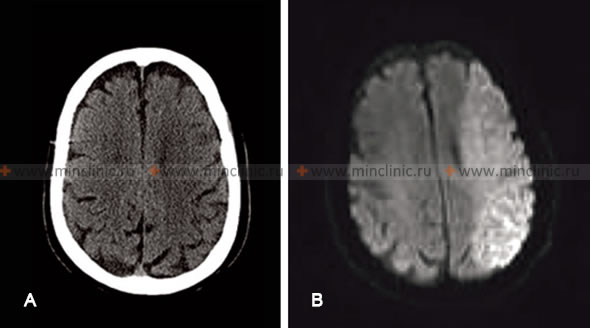

A. КТ головного мозга (без контрастирования) без признаков острого инфаркта, несмотря на наличие синдрома закупорки левой средней мозговой артерии (СМА) у пациента при осмотре. B. МРТ головного мозга того же пациента, проведённое через 0,5 часа, показывает ишемический инсульт в бассейне левой средней мозговой артерии (СМА).